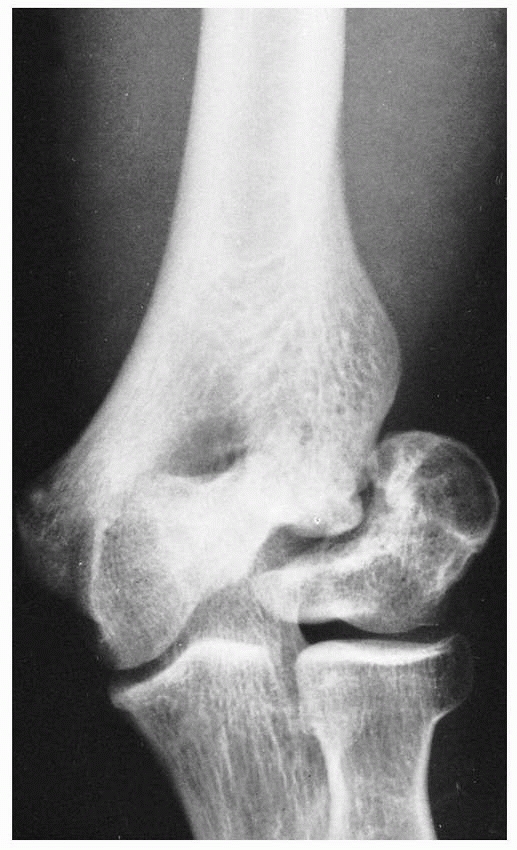

![]() |

FIGURE 15-12 Delayed union and cubitus varus. A. Stage III lateral condylar fracture in a 7-year-old boy was treated in a cast. B. Seven months later, delayed union with malunion of the fracture and cubitus varus deformity was present.